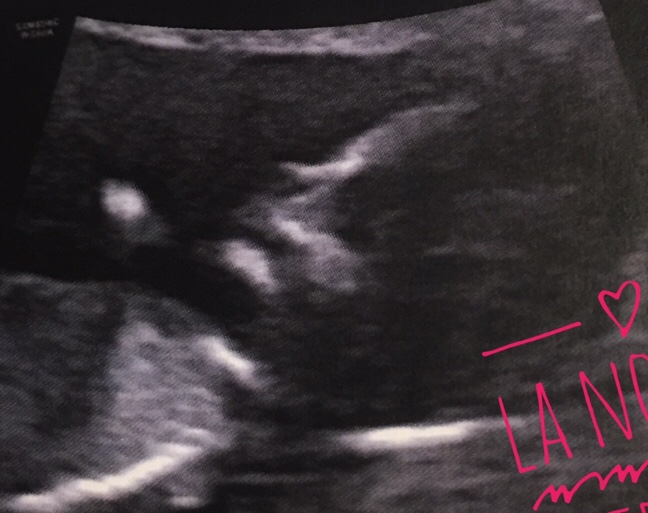

Mi sono ingrassata, ma forse avvolta in strati di nero non si vede troppo. E non riesco ancora a liberarmi di quella panciotta, che ogni tanto involontariamente accarezzo. È la stata la tua casa, la tua culla, ancora non ce la faccio a lasciarla andare.

Mi sento così, un involucro che ha custodito la vita, ma non è stato capace di proteggerla fino in fondo, non è stato capace di nutrirla bene, di farla crescere sana.

Chissà anche in gratitudine poter averti comunque avuta, seppur per così poco, con me, mia piccola, dolcissima Vittoria.